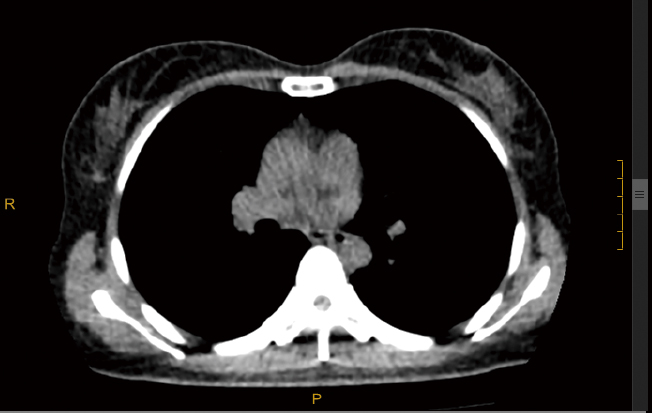

临床展示